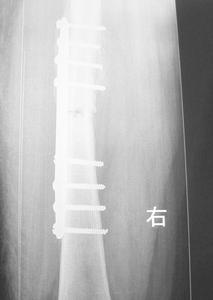

A組:24例採用切開復位DCS內固定。連續硬膜外麻醉,股外側縱切口,切開皮膚及闊筋膜,分離股外側肌,切開骨膜並行骨膜下剝離,充分顯露骨折端。先將髁部骨折復位,使關節面達到解剖復位,用克氏針或持骨鉗將骨折塊固定,再將髁與乾復位,取髁外側股骨長軸線上距遠端關節面2cm為進針點,用95°髁導向器定位,由外向內平行於前髁關節面打入導針,X線證實位置良好,用DCS鋼板模擬測試後,三聯鑽鑽骨,測深、攻紋,擰入動力髁釘、套入鋼板,用持骨鉗將鋼板夾在股骨幹上,分別擰入其它皮質骨螺釘,最後擰緊加壓螺釘尾。有骨缺損者常規植骨。B組19例採用髁鋼板內固定。手術方法基本同前,不同處是:

術後不用外固定,傷口內放置引流,48h~72h拔除。拔引流後即開始股四頭肌鍛練,A組同時開始CPM功能鍛練,B組4W開始CPM功能鍛練。4W開始扶雙拐不負重下地活動,10W~12W開始練習負重行走。

所有病例進行了隨防無感染髮生,全部骨性癒合骨折癒合時間為8W~24W,平均12W,A組膝關節功能:平均伸0°∥屈130°無膝內外翻,B組:伸0°∥屈120°8例合併膝內翻。討論

DCS具有抗彎、抗扭曲、抗剪力及抗鏇轉作用,能使髁間骨折塊加壓、有良好的力學穩定性,固定可靠、牢固堅強,有利於關節早期活動。DCS為95°釘板結合,符合股骨遠端的解剖結構,適用於股骨髁上、髁間骨折、操作時只需在兩個方向精確安裝,操作簡單、鋼板易於與骨幹軸線一致,便於復位。採用DCS系統固定時內固定物不需要敲擊,只需沿導針滑動,從而保證內植物前進方向。但DCS也有它的局限性,對老年骨質疏鬆症嚴重的應慎用。在動力加壓螺釘和鋼板結合部突出,同時不適用於髁部粉碎性骨折。

綜上所述DCS是治療股骨髁上骨折的手術方法中,固定最穩定、療效較可靠的動力髁固定系統,如能正確掌握適應證,術中準確操作、可以取得良好的治療效果。